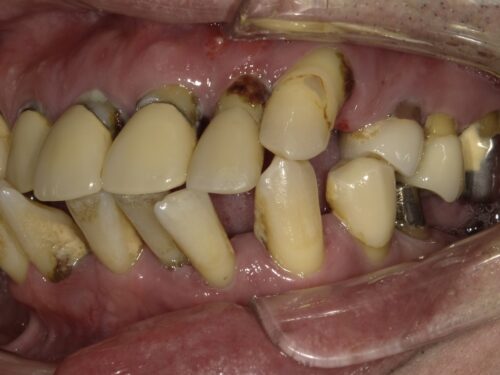

歯周病で歯がグラグラしてしまって来院された患者さんです。

グラグラしてる影響か、前歯が傾いてきてしまっています。

歯ぐきの周りに歯石がついているのが見えます。

歯ぐきも赤く腫れ上がっていますが、

奥歯も残っていますが歯周病で根元まで見えてしまっていたり、

歯の向きが変わってしまっているところもあります。

下の大臼歯とよばれる奥歯はもうありませんでした。